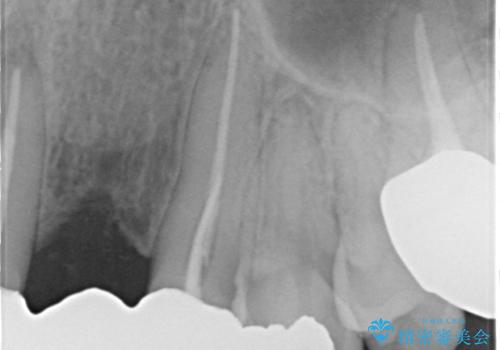

- 昔入れた被せ物と歯茎の間の隙間が気になると来院された方の症例です。

右上1、2番目の歯と左上1、2、3、番目の歯のブリッジを除去し、オールセラミッククラウンによる補綴を行うことで見た目を改善しました。

根管治療の注意事項(リスク・副作用など)

- 根管治療により類似の全ての症例の問題が解決するわけではなく、症例はあくまでも一例です

- 根管治療により痛みや腫れがひかない事や、術後に痛みや腫れが生じる事、治療によるファイル破折やパーフォレーションなどの偶発症、術後の歯根破折を生じる可能性もあります